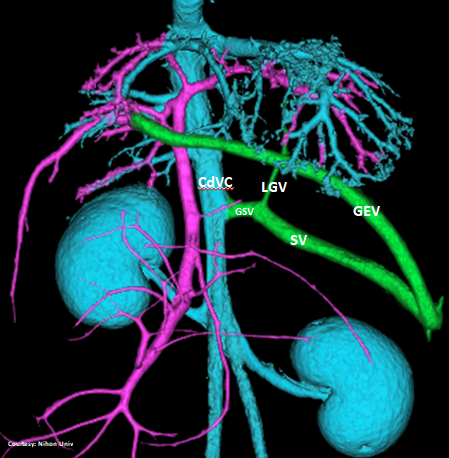

“LGC +RGV +SGV”

Left Gastro-Caval Shunt with Right Gastric Vein and Short Gastric Vein contributions

Courtesy: Nihon Univ